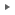

移動中の写真です。

下顎の犬歯が上顎の切歯と犬歯の間に入るようにカバーをします。

前述の写真のコメントです。下顎犬歯カバーにより犬歯を適正な位置に移動させます。